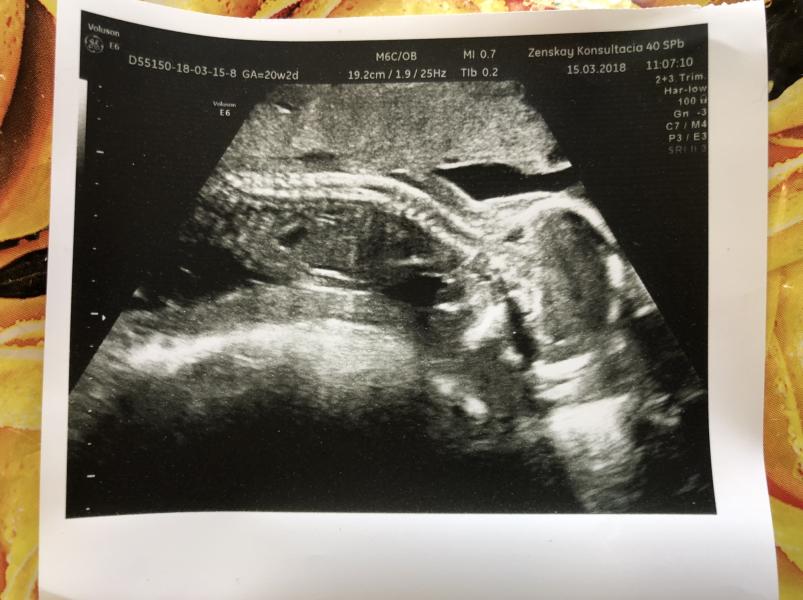

И так что имеем, сходила я значит на третий скрининг и там всех хорошо ттт, но мой малыш уже третье УЗИ лежит лицом к моей спине, вот фото это второй скрининг.

На УЗИ 3D так же ходила к Чабоняну и он сказал что у меня тонус (но в ЖК мне говорят тонуса нету😶 и крутят у виска), а Чабонян сказал, малыш так лежит потому что тонус.

А сегодня узистка сказала что тонуса нет, малыш так и должен лежать.